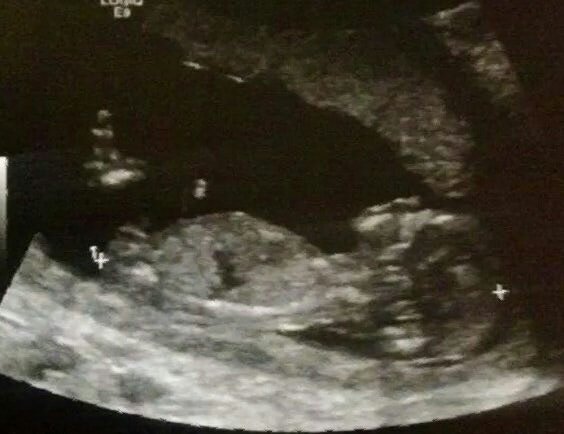

This scan was taken at 14weeks,

I find out the gender in 2weeks(:

What do you guys think?

Girl :)

Girl

Girl!